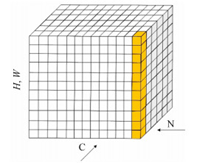

在深度神经网络中,网络的层数较深,不同层之间的神经元相互影响.若在网络的某一层数据发生抖动偏移,随着网络的加深数据抖动的问题会愈加强烈,从而影响模型的训练优化过程,归一化可有效缓解数据震荡的问题.目前常用的数据归一化方法有批量归一化(Batch Normalization, BN)、全局归一化(Group Normalization, GN)、权值归一化(Weight Normalization, WN)以及实例归一化(Instance Normalization, IN)等.在本实验中训练集和测试集的batch大小均设置为1,而BN、LN和WN均是针对于batch值较大的情况,而IN能够处理batch值较小的情况,因此采用IN对脑肿瘤数据进行归一化处理,在解决数据抖动的同时加快脑肿瘤检测网络的收敛速度.IN方法的示意图如图 5所示.

图 5 实列归一化方法示意图

图 5从N看过去是一幅幅脑肿瘤图片,从C方向看过去是脑肿瘤特征图的像素点.每11个竖着排列的小正方体组成的长方体代表一幅脑肿瘤图片的一个特征图.深色方块是一起进行归一化的部分,由此可以很清楚地看出IN是指单张脑肿瘤图片的单个通道单独进行归一化操作.